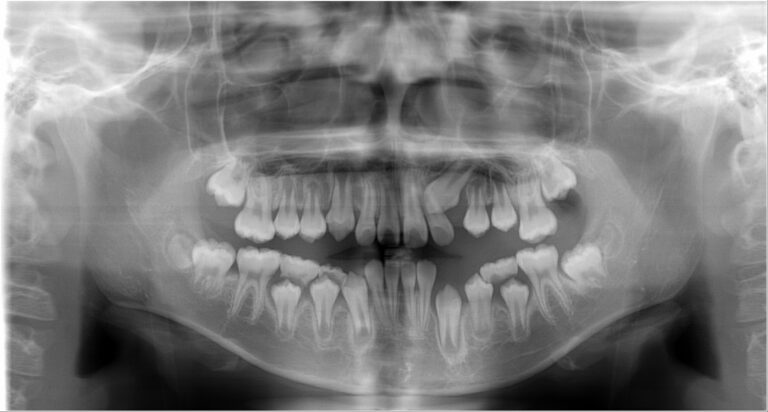

永久歯が生え揃ったら

永久歯が揃い成長が一段落したところで、第二段階の歯並びの治療が必要か検査を行います。第一段階で良好なコントロールができた場合、第一段階で終了することがあります。機能的な咬合を確立し、歯が動かし終わったところで、後戻りを防ぐ治療(歯固め)が行われます。

矯正治療に必要な各種検査を行います

必要に応じてレントゲン撮影、歯型取り、写真撮影、CT撮影などを行います。所要時間は1時間程度です。

乳歯が萌えかわり、身長の伸びのピークを迎えたら、第一期治療の評価を行います。その後、第一期治療で終了する子と、第二期治療に移行する子に分かれます。